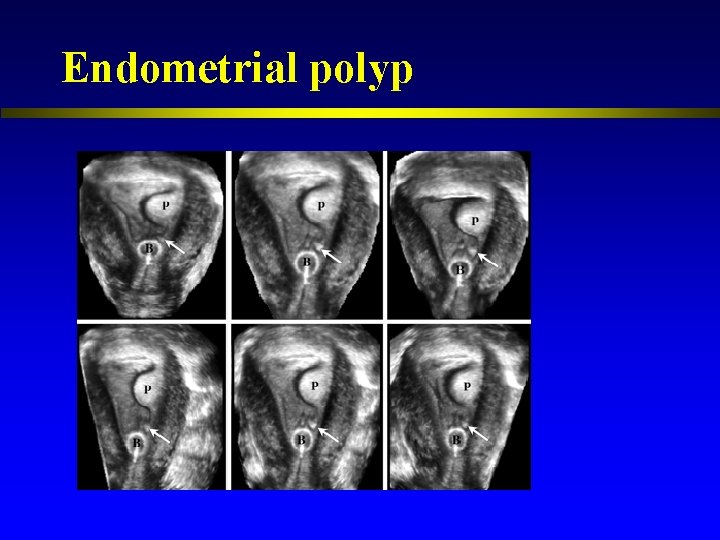

Endometrial polyp

Endometrial polyp